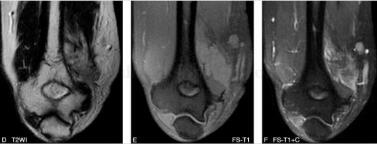

滑膜肉瘤(图4)

图4 病理:镜下:瘤细胞部分圆形,部分梭形,异型明显,间质有黏液,浸润性生长,有较多坏死。免疫组化:CK(+),Vimetin(+),Bcl-2(±),S-100(-),CD34(-),MyoD1(-),SMA(少许+)。诊断:(肘部)滑膜肉瘤